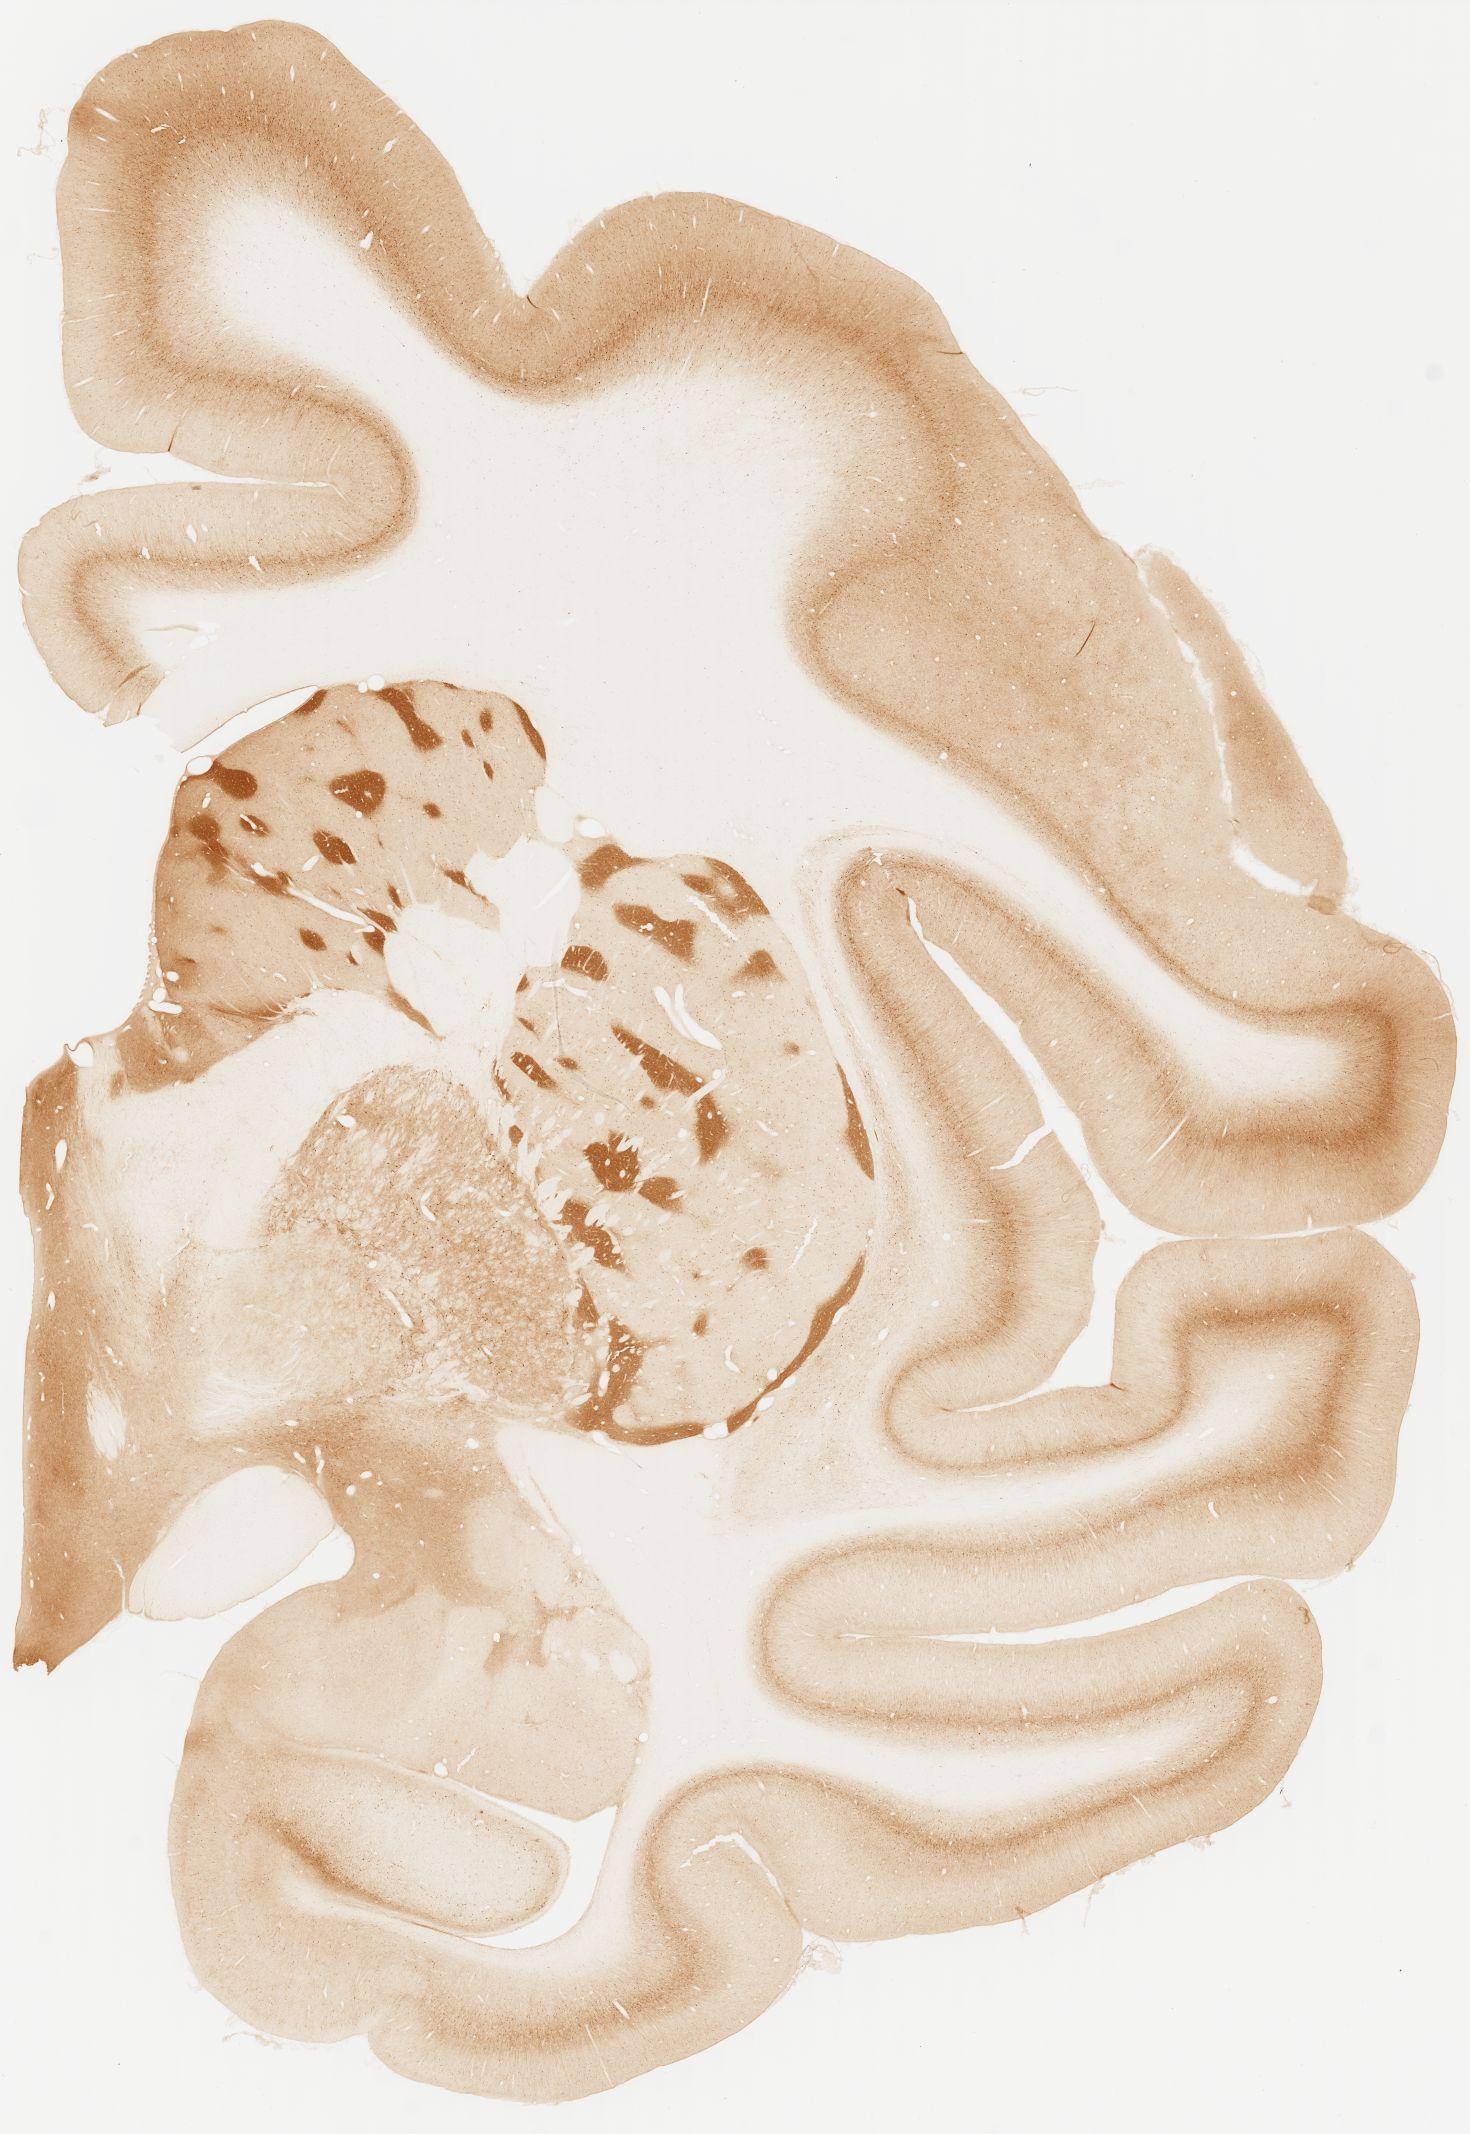

Datasets -> Macaca Fascicularis -> KChIP1, (Potassium Voltage-Gated Channel-Interacting Protein 1), coronal, immuno, Whole-Brain, adult

[ Metadata ]   ·   Source: Edward G. Jones